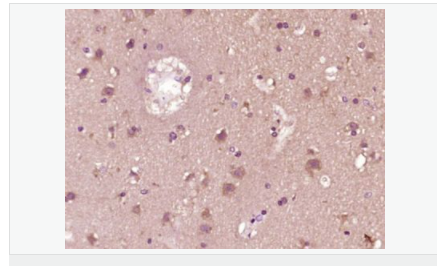

交叉反應:Human,Mouse,Rat(predicted:Pig,Cow,Horse) 推薦應用:WB,IHC-P,ICC,ELISA

| 產品應用 | WB=1:500-2000 ELISA=1:5000-10000 IHC-P=1:100-500 Flow-Cyt=1ug/test (石蠟切片需做抗原修復) not yet tested in other applications. optimal dilutions/concentrations should be determined by the end user. |